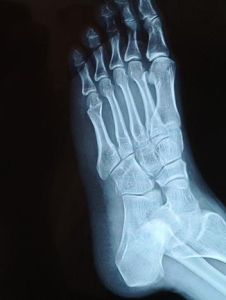

跖骨:跖骨近側為底,中部為體,遠側端為頭。

辭海中的解釋,組成足底的小型長骨。相當於手的掌骨。介於跗骨與趾骨間。

人體位置在人體中,每足有五塊,連於踇趾的稱第一跖骨,以下依次為第二至第五跖骨。

跖骨多數人認為本病發病多半與外傷有關,而積累性勞損較單次損傷的可能性大,活在 跖骨頭關節面的 骺板和 關節軟骨不全骨折的基礎上產生。也有人認為由於第2跖骨長於其他跖骨,而且在第二跖骨近端又被第三快契骨所包繞,活動度最小,負重時跖骨頭承受應力最大,故易導致缺血壞死。另外,女孩足部 肌肉力量較弱,足弓較低,造成2、3跖骨頭骨骺負重更多,這可能為本病多見於8-17歲女孩的原因。

本病多見於青少年,一般多在13歲以後發病,尤以8-17歲的女孩多見,約占75%。左右測發病相近,10%為雙側同時發病。多見於第二跖骨頭,遇見其他跖骨頭。受累的跖趾關節常過伸,活動明顯受限制,強行屈曲或用足尖著地時,疼痛加重。有事可觸及跖骨頭粗大、壓痛。病人足弓較低,橫弓鬆弛,或伴有輕度跛行。後期因跖骨頭膨大,關節面不平整,有骨贅增生而壓迫其下趾神經,引起持續性疼痛,關節和有摩擦音。